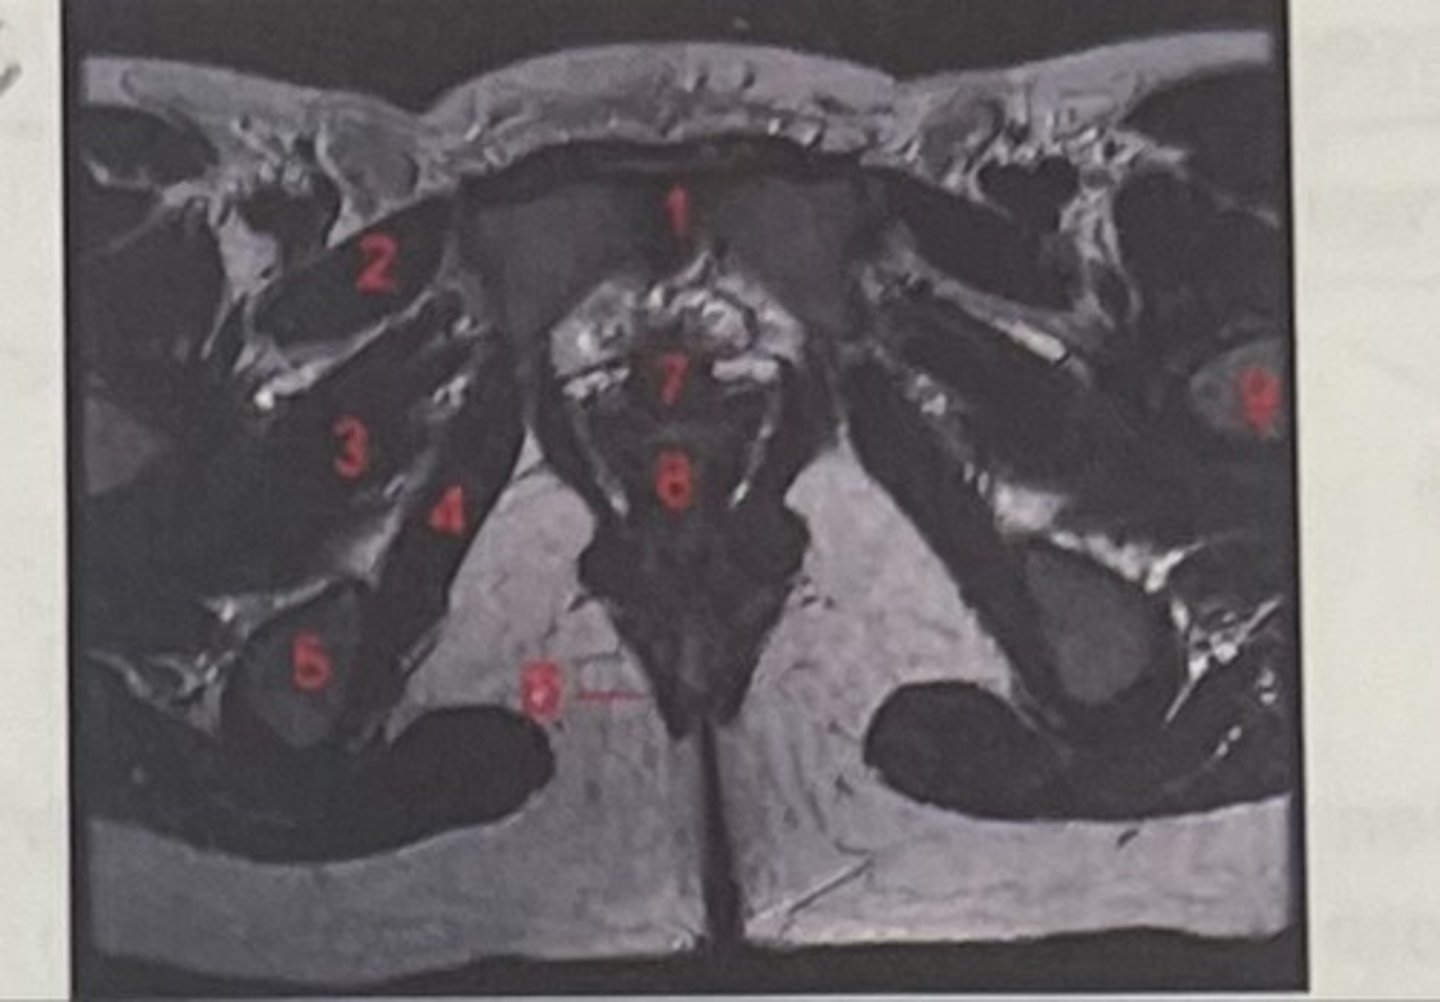

pubic symphysis

What is 1

Pectineus

What is 2

Obturator externus

What is 3

obturator internus

What is 4

ischial tuberosity

What is 5

external spincter

What is 6

Urethra

What is 7

Vagina

What is 8

Femoral nerve

What is 9

Left lung